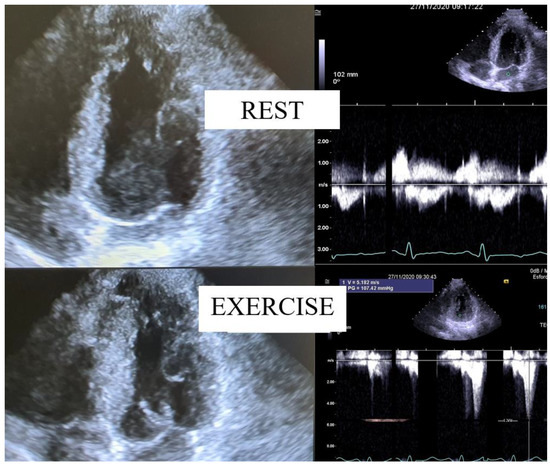

| [27] | As various types of exercise have different consequences on peripheral vascular circulation, this study sought to compare upright treadmill exercise echocardiography (EE) to semi-supine bicycle EE in maximum provoked LVOTO in HCM patients. | 23 HCM | Comparative study | This study demonstrates that, when compared to the semi-supine bicycle EE, the treadmill is better for ascertaining the maximum LVOT gradient in HCM. |

| [40] | The relation between functional capacity and exercise-induced LVOT obstruction in HCM is incompletely defined. The time course of the provoked gradients and the relation to exercise performance were assessed. | 74 HCM | Research | In patients with non-obstructive HCM at rest, the earlier onset of LVOT gradients during treadmill exercise was associated with impaired exercise performance. These findings have yielded insights into the determinants of functional impairment in HCM and support the potential value of exercise echocardiography in the clinical evaluation of patients with HCM. |